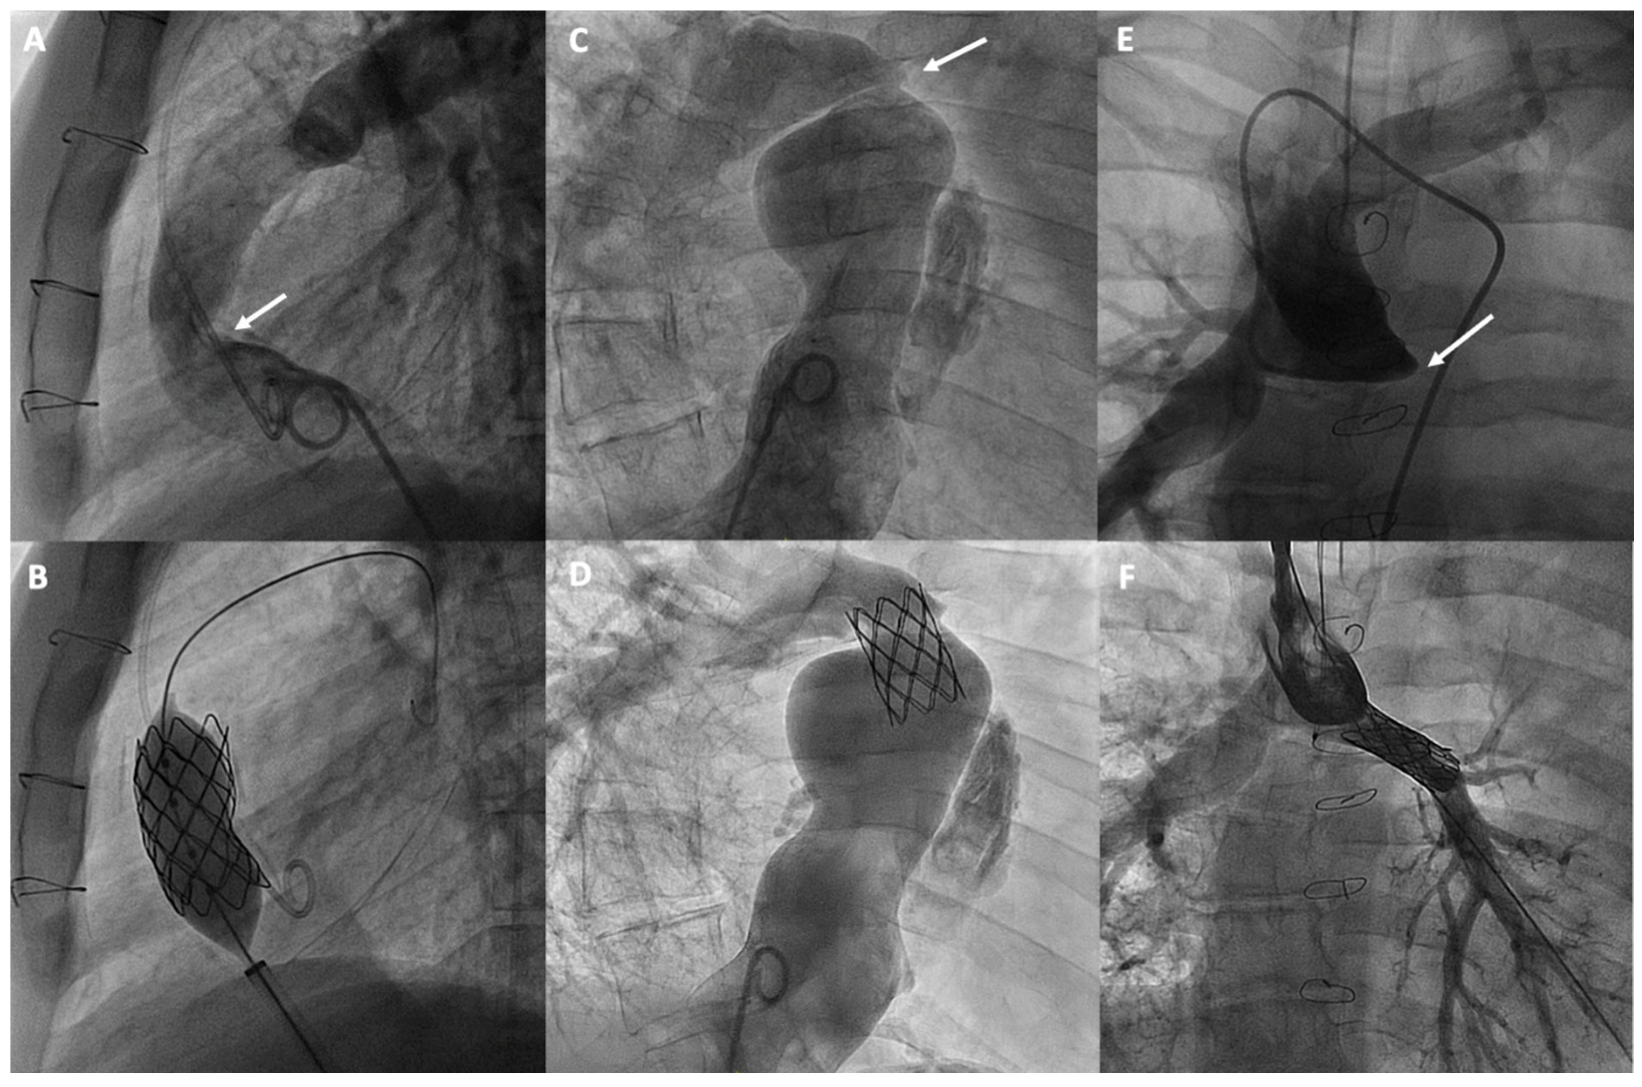

Figure 4.

Percutaneous treatment of Fontan pathway obstructions with stent angioplasty on (A,B) an obstructed extracardiac Fontan conduit, on (C,D) an atriopulmonary anastomosis in classic Fontan, and on (E,F) a complete occlusion of the left pulmonary branch artery. The arrows in each figure indicate the point of obstruction or occlusion.

Angiographic studies or non-invasive imaging tests, such as cardiac magnetic resonance (MR) or computed tomography, can facilitate the diagnosis, localization, and assessment of the severity of the obstruction to plan their treatment [58]. There are uncertainties regarding which obstructions should be treated and how to assess their severity. Small gradients may be functionally relevant, and if they are accompanied by significant stenosis, they should be considered for treatment. Functional assessment through exercise catheterization can reveal gradients that are otherwise insignificant at baseline [15].

Currently, stenting is the most commonly used technique, with a high success rate and safety, for treating obstructions in the various substrates of the Fontan [59] and proximal pulmonary branches, leaving balloon angioplasty for selected cases or for treating more distal pulmonary arteries [60] (Figure 4). Pre-dilation is generally not recommended, especially if there is a risk of rupture. However, high-pressure post-dilation is advised to optimize stent placement in cases of under-expansion. The use of covered stents is recommended for calcified conduits at risk of rupture, while bare-metal stents are preferred for treating pulmonary branches to avoid the risk of jailing side branches [60].

Figure 5.

Percutaneous intervention in cyanotic patients due to right-to-left shunt: (A,B) Fenestration closure; (C,D) Veno-venous shunt closure from a persistent left superior vena cava (LSVC) to the coronary sinus (CS). The arrows in each figure indicate the shunt and its closure with an occlusion device.